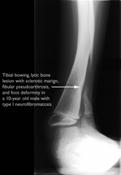

- Curvatura congénita de la tibia o peroné (huesos de la pierna): huesos curvados, más finos de lo normal, que se fracturan con facilidad y la fractura no llega a consolidarse. Se puede dar también en el brazo. También recibe el nombre de pseudoartrosis.